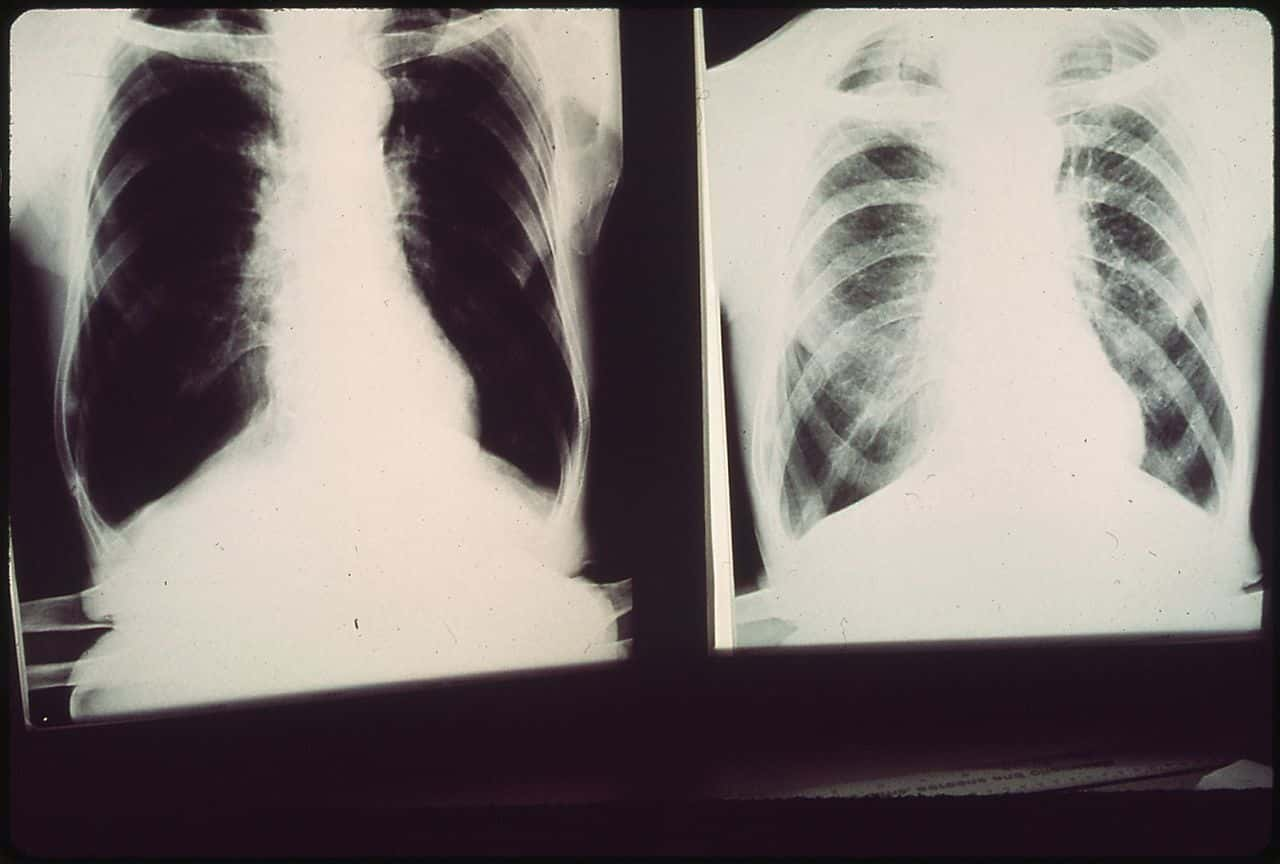

#30 Collapsed Lung

I once went to the hospital because I thought I had a collapsed lung. Turns out I was just super hung over and my ribs hurt from throwing up all night. Very embarrassing and expensive.